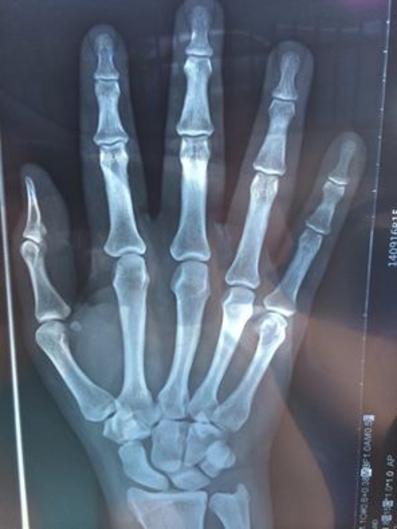

La aguja. No toda entra al hueso. Es así de larga pq cada cuerpo es diferente. Algunos son más "saludables" q otros.

Me puñalearon 3 veces por la clavícula derecha pa meterme esto (a ver si sale mañana en El Vocero):

El catéter lo instalan debajo de la clavícula derecha. Por ahí sucede todo: colección de CM, quimio, infusión de CM y muestras de sangre para laboratorios.